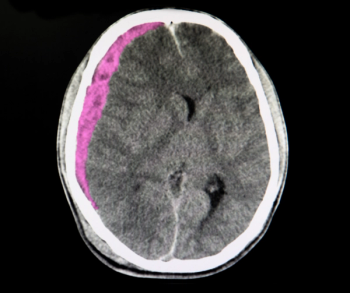

Powered by artificial intelligence (AI), the Rapid NCCT Stroke modality is reportedly the first medical device to gain FDA 510(k) clearance for detecting suspected large vessel occlusion and intracranial hemorrhage based on assessment of non-contrast computed tomography (NCCT).

The artificial intelligence (AI) triage and notification indications include acute subdural/epidural hematoma and acute subarachnoid hemorrhage for head computed tomography (CT) imaging.